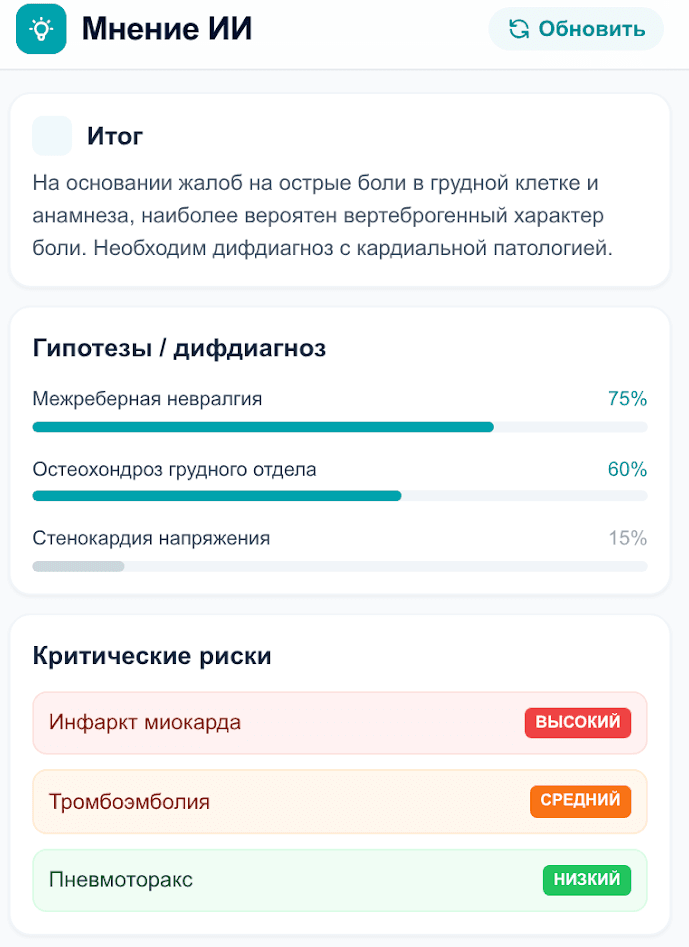

NexusMed помогает врачу быстрее принимать клинические решения: находит релевантные рекомендации, анализирует снимки и дает дополнительную опору во время приема.

Второе мнение для врача от ИИ

ИИ помогает быстро проверить клиническую гипотезу и получить дополнительную опору для принятия решения во время приема.